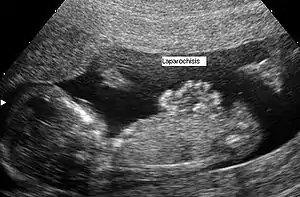

![]() УЗД картина гастрошизіса, продемонсторвано в сагітальній площині УЗД картина гастрошизіса, продемонсторвано в сагітальній площині | |

Гастрошизис, як правило, діагностують пренатальльно за допомогою УЗД.